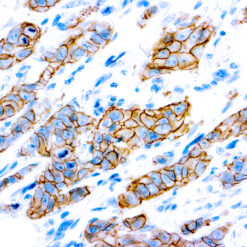

Leukocyte Common Antigen (LCA)/CD45

CD45R, also designated CD45 and PTPRC, has been identified as a transmembrane glycoprotein, broadly expressed among hematopoietic cells. Multiple isoforms of CD45R are distributed throughout the immune system according to cell type. These isoforms arise because of alternative splicing of exons 4, 5, and 6. The corresponding protein domains are characterized by the binding of monoclonal antibodies specific for CD45RA (exon 4), CD45RB (exon 5), CD45RC (exon 6) and CD45RO (exons 4 to 6 spliced out). The variation in these isoforms is localized to the extracellular domain of CD45R, while the intracellular domain is conserved. CD45R functions as a phosphor-tyrosine phosphatase. Antibody to CD45 is useful in differential diagnosis of lymphoid tumors from non-hematopoietic undifferentiated neoplasms.

| Cellular Localization | Cell membrane and Cytoplasmic |